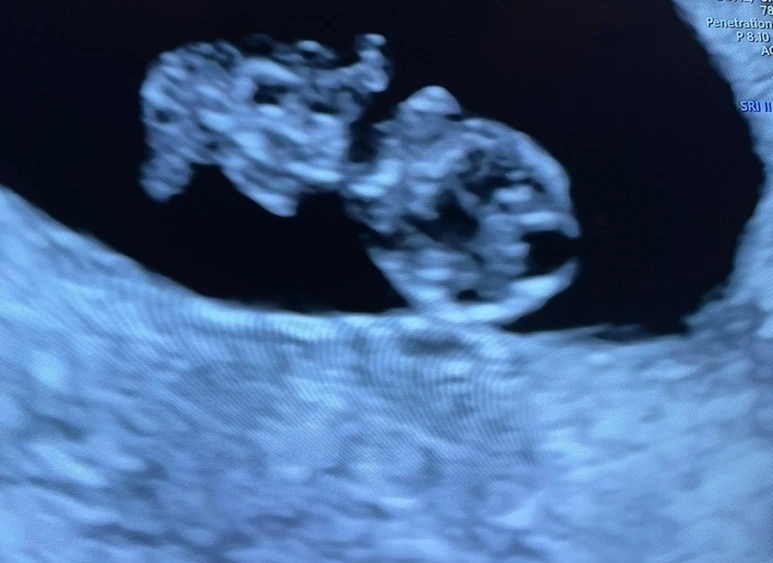

미국 생활이 조금 안정되고 내가 일을 쉬고 있는 지금 아이를 갖는 것이 좋을 것 같다는 생각으로 우리는 아이를 계획하였다. 이전에는 임신이 이렇게 어려운 것인지도, 난임이나 유산으로 고생하는 사람이 많은지도 잘 알지 못했다. 임신이 되는 과정들을 찾아보며 아이를 갖는 것이 엄청난 확률로 이루어지는 기적과도 같은 일이라는 것을 알게 되었다. 다행히 아이가 바로 우리에게 찾아왔고 임신을 확인한 그날은 아직도 잊지 못할 정도로 엄청난 감동이었다. 내 몸 안에 하나의 생명이 자라나고 있다는 것은 말로 표현할 수 없을 만큼 엄청나게 가슴 떨리는 일이었다. 매사에 감사하는 마음이 더 커졌다.

다행히 입덧약을 먹고, 임신의 꽃이라는 중기가 찾아오면서 몸이 조금씩 호전이 되어 갔다. 그리고 신기하게 내게 모성애라는 것이 조금씩 생겨나고 있었다. 무엇을 하기 전에 항상 뱃속의 아이를 먼저 생각하며 조심하게 된다. '모성애라는 것이 생기지 않으면 어떡할까, 나중에 아이가 속 썩이면 나는 현명하게 잘 대처할 수 있을까'하는 사소한 걱정들이 눈 녹듯 사라졌다. 검진 때마다 아이의 심장소리를 듣고, 자기 전 태동을 느끼며 부부가 아니면 공유하지 못하는 우리만의 추억도 힘든 임신을 극복할 만큼 엄청 소중하다. 이전에 겪어보지 못한 다양한 감정들을 겪으며 나도 이제야 어른이 되어 가는 것 같은 기분이다. 힘들지만 임신은 상상할 수 없는 행복을 가져다주는 것 같다. 앞으로 5개월 정도 남은 시간 동안 아이가 건강하게 잘 자라 무사히 출산을 할 수 있었으면 좋겠다.